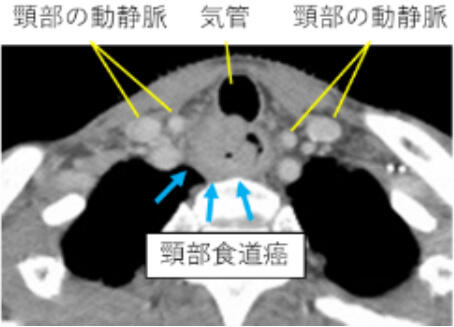

解剖学的に頸部食道は咽頭からつながる約3cmの食道で前方に喉頭/気管と密着しており、ここに癌ができると、癌から距離が取れない、癌が気管浸潤する、嚥下障害が出るなどの理由で、喉頭も一緒に切除することが一般的で、ゆえに標準術式は、咽頭喉頭頸部食道切除とされています。しかし癌治療のためとはいえ、声を失うことは患者さんにとって可能なら回避したい大きなテーマです。

癌の位置、浸潤程度で喉頭温存できるか決まります。食道入口部直下なら可能性あり、後壁なら咽頭に一部癌が浸潤していても可能性はあります。手術の技術と工夫で温存できる限界を広げて実現します。ただし気管浸潤がある場合は温存手術適応外となります。(東京医学社 消化器内視鏡 28 115-121 2016年1月)